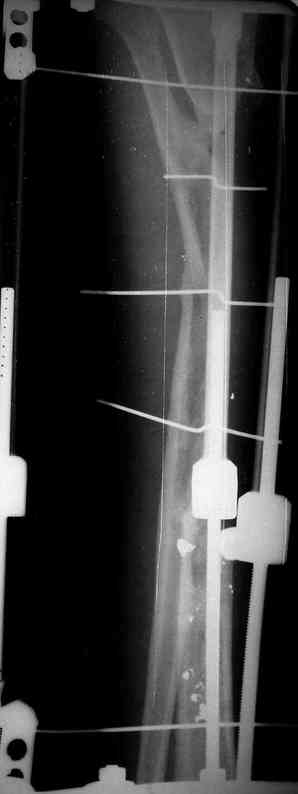

5. Ну и чтобы не быть голословным. Молодой человек подорвался на фугасе (Чечня, 2005 год). Свежие рентгенограммы:

Соответственно ожоги и дефект мягких тканей, переломы костей стопы и пр. Наложили аппарат

Илизарова (как придется), хирургически обработали и героически заживляли мягкие ткани с многочисленными кожными пластиками. В итоге через полгода я принял его вот таким:

Реализовал описанную выше методику, и в итоге вот что получилось. Высылаю лишь прямые проекции,

Очень пригодились карбоновые кольца (Джолдас -огромное спасибо, я твой должник!!!), поскольку остеопороз дистального отломка был просто невероятный. На цифровом рентгене с трудом угадывались контуры.

Рентген в процессе перемещения - внизу карбоновые кольца, тракция фрагмента спицами с упором.